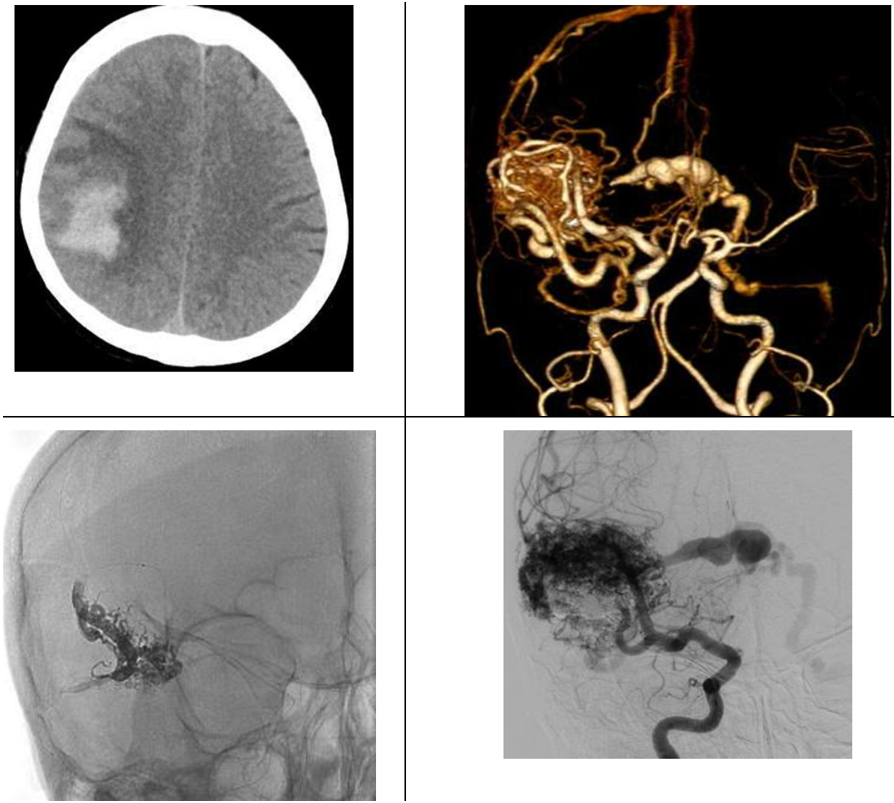

Thái độ xử trí đối với dị dạng thông động-tĩnh mạch não đã được hiệp hội Tim mạch và đột quỵ Hoa Kỳ đưa ra vào năm 2017. Nút mạch đối với dị dạng AVM có xuất huyết não cấp thường đặt ra để điều trị chảy máu do phình mạch cạnh ổ nidus dị dạng hoặc nút tắc chọn lọc điểm chảy máu giảm nguy cơ chảy máu tái phát. Sau giai đoạn cấp khi mà khối máu tụ đã tiêu hết (khoảng 4-6 tuần), thì việc nút mạch điều trị dị dạng AVM tùy thuộc vào mục tiêu cụ thể cho từng bệnh nhân bao gồm nút mạch triệt để dị dạng (qua đường động mạch hoặc tĩnh mạch), nút mạch giảm một phần thể tích nidus trước mổ giúp giảm nguy cơ phẫu thuật hoặc nút mạch một phần dị dạng phối hợp với xạ phẫu.

Bệnh nhân nữ 67 tuổi có xuất huyết lớn trong nhu mô thái dương-phải do dị dạng AVM vỡ. Dị dạng mạch này được can thiệp nút tắc chọn lọc một phần chảy máu bằng Onyx.